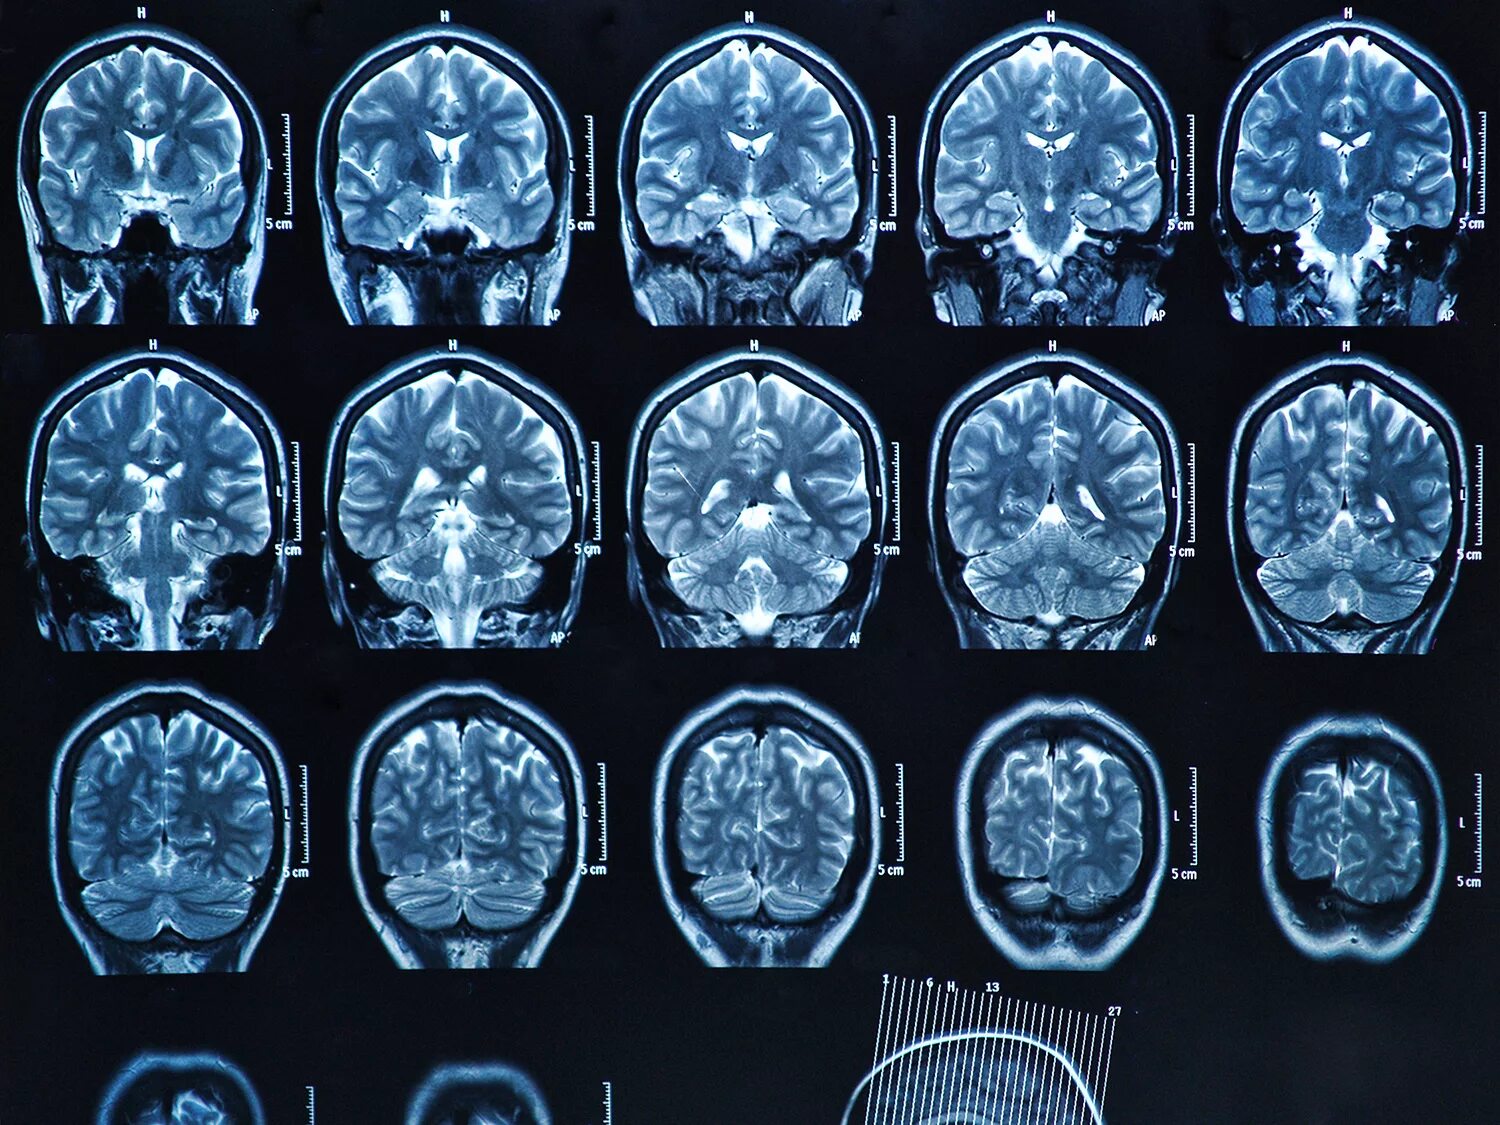

После мрт головного мозга